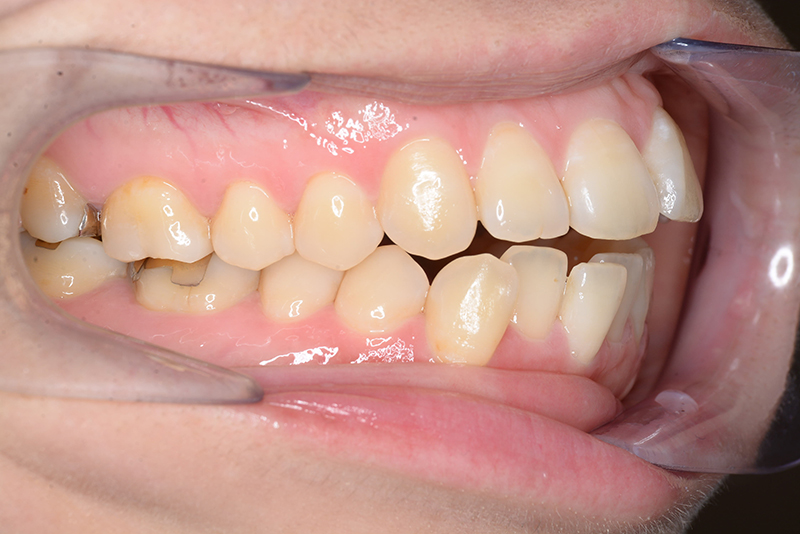

| 口腔内所見 | 臼歯関係はⅠ級、over jet 4.5mm、over bite -3.0mm。上下顎切歯部に軽度の叢生が認められ唇側傾斜をしつつ開咬を呈していた。 |

| 批評・予后 | 治療後において下顎角の開大も認められず歯軸の整直、咬合の緊密化が得られた。また上下顎前歯の後退と共に口元の突出感と口唇閉鎖不全の改善が認められた。 |